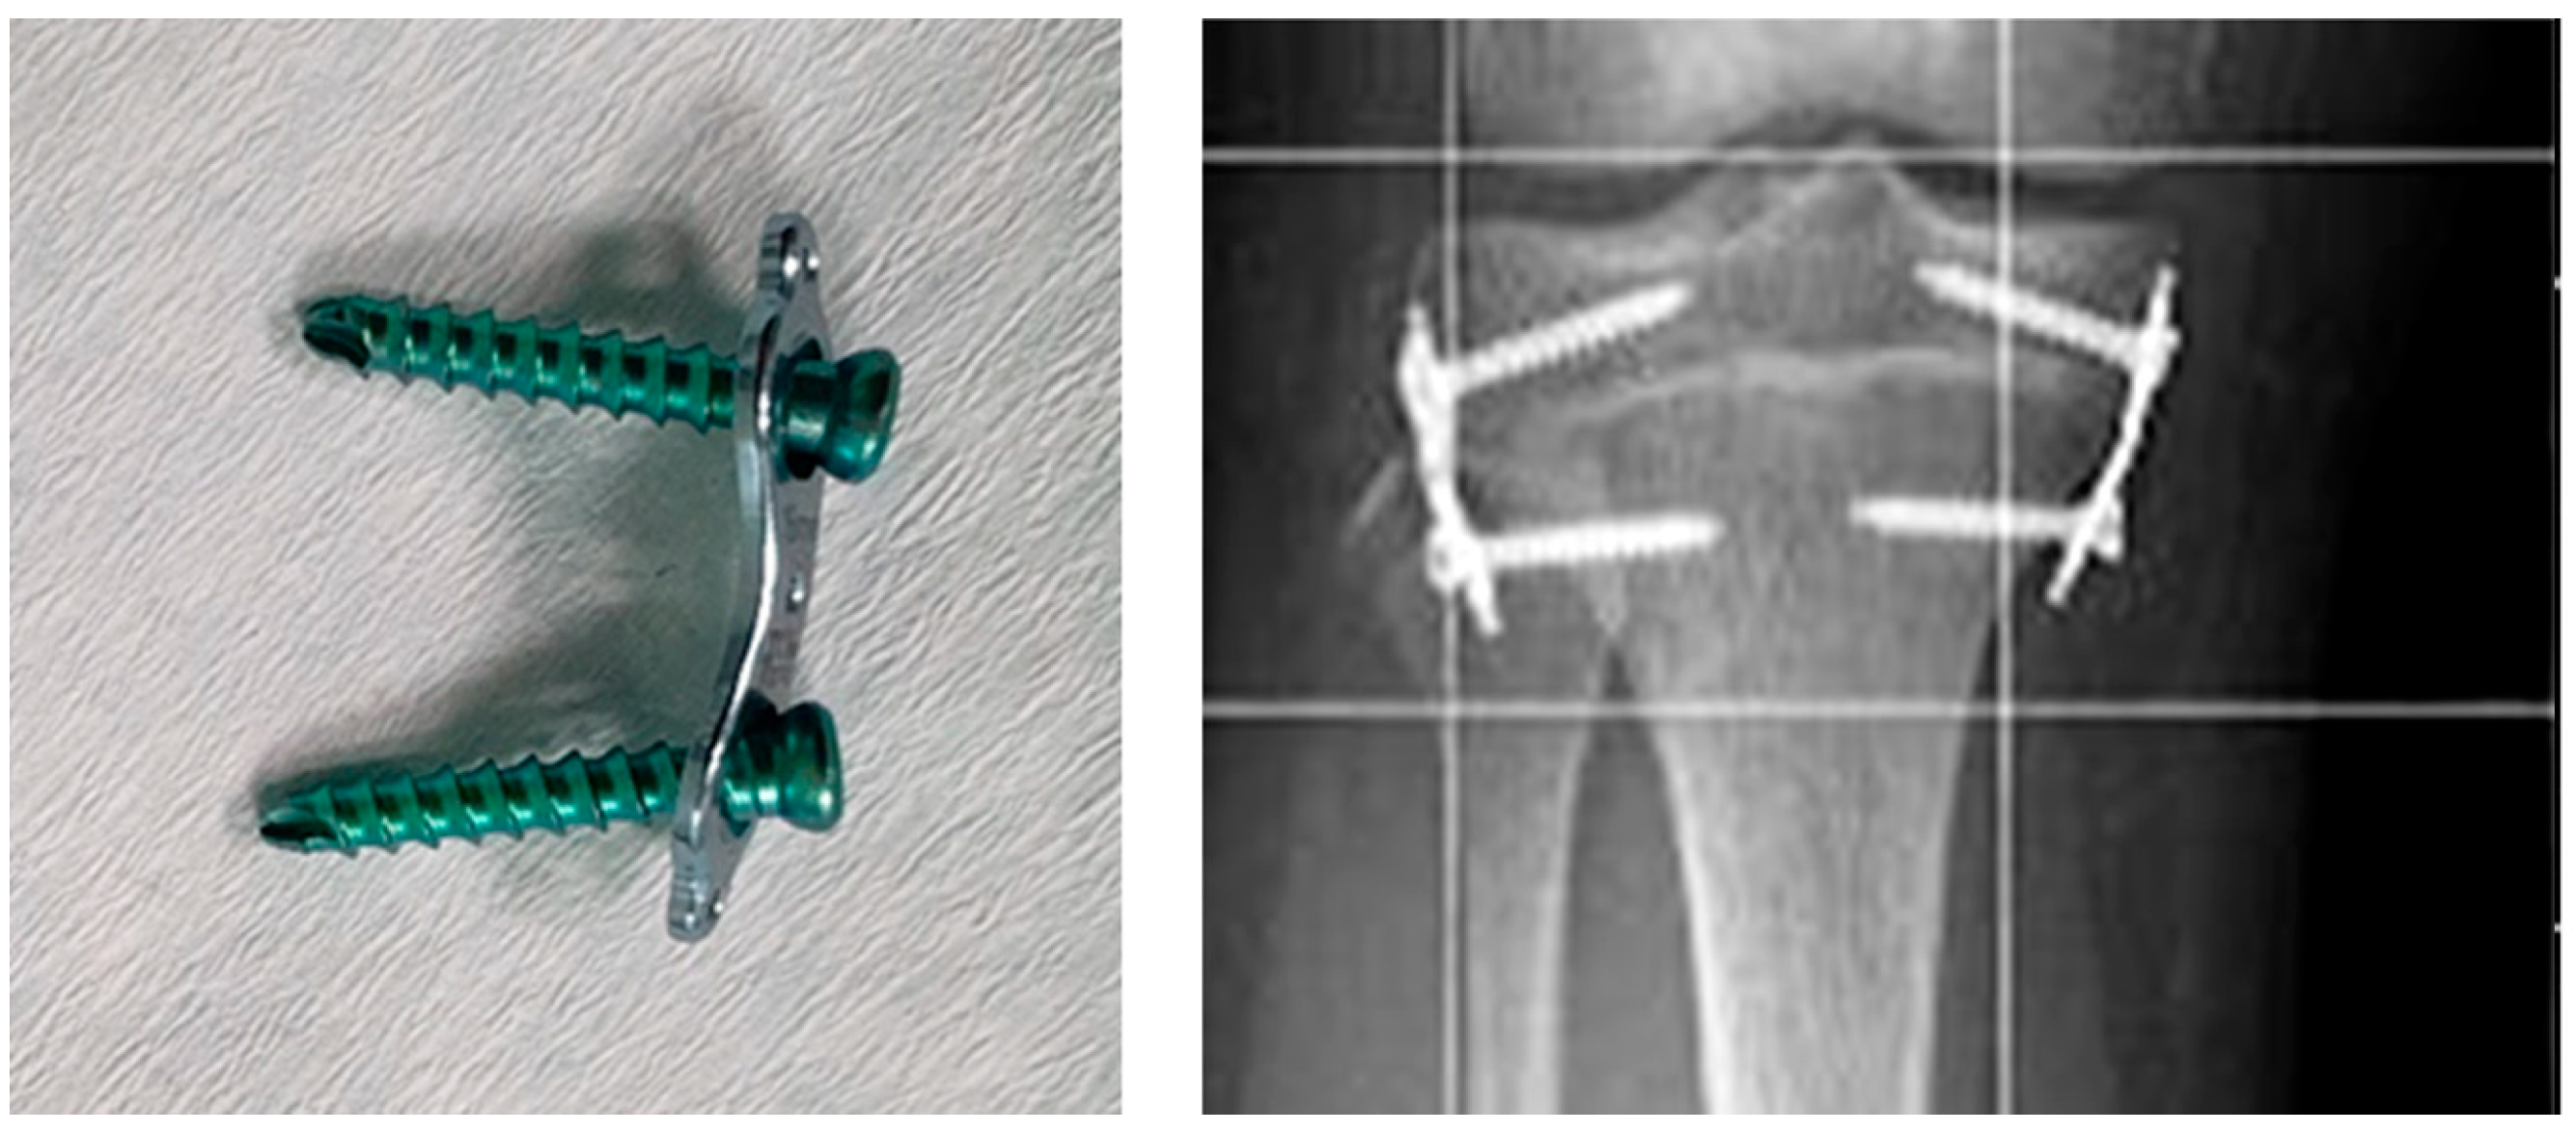

Epiphysiodesis with flexible plates in the shape of the figure “8” and two screws (Figure 1) was introduced in 2007 by Stevens (Orthofix; McKinney, TX, USA).

Figure 1.

Eight-plate implant and X-ray image of the knee joint showing eight-plate implants used for the treatment of leg length discrepancy.

These implants were developed as a response to complications that occurred when using Blount staples. The strong compression with a stiff pin damaged the growth plate, which prevented it from functioning after the implant was removed. Other complications included damage or dislodgement during treatment [6].